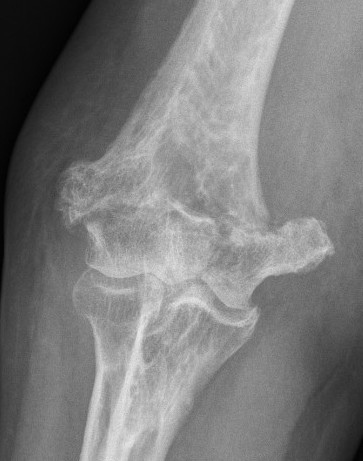

OTA / AO Classification

Type A: Extra-articular fracture

Type B: Partial articular fractures

Lateral condyle Medial condyle

Type C: Complete articular fractures

CT scan